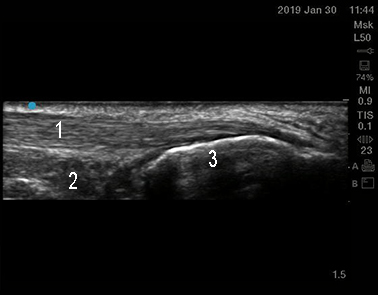

Foot & Ankle Achilles Tendon 2 Image

Achilles Tendon

Kager's Fat Pad

Calcaneus